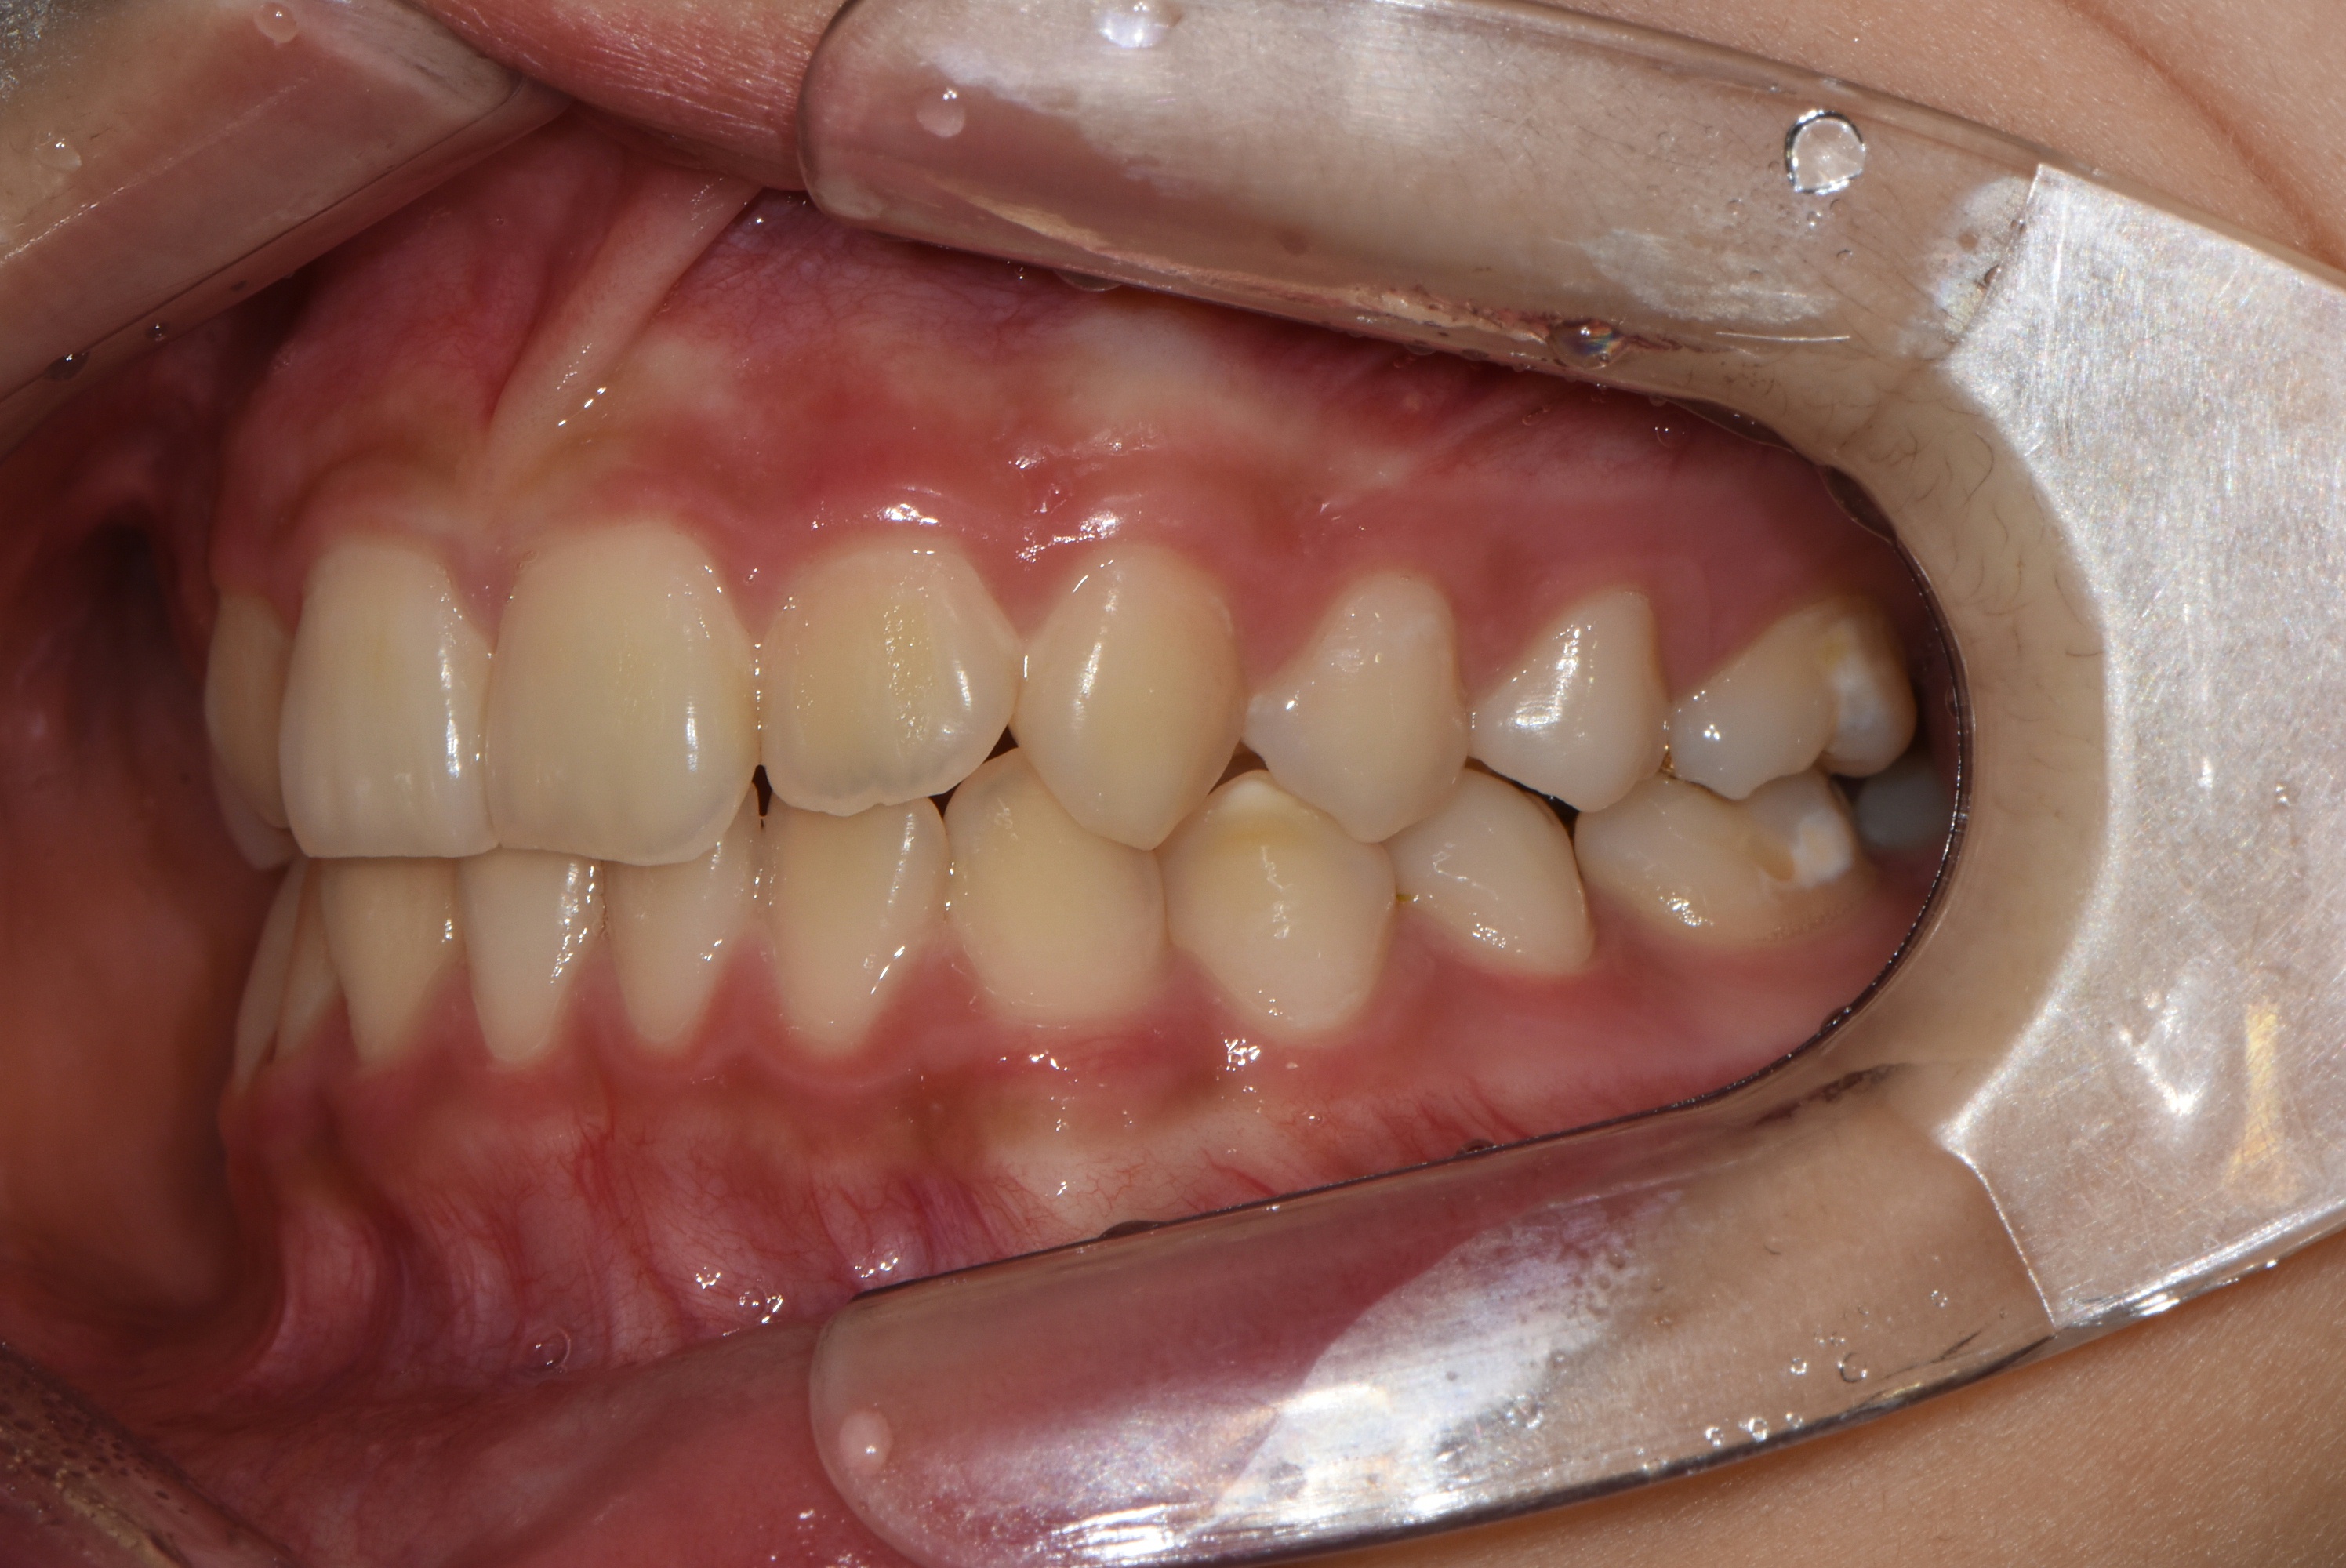

치료 전 사진입니다.